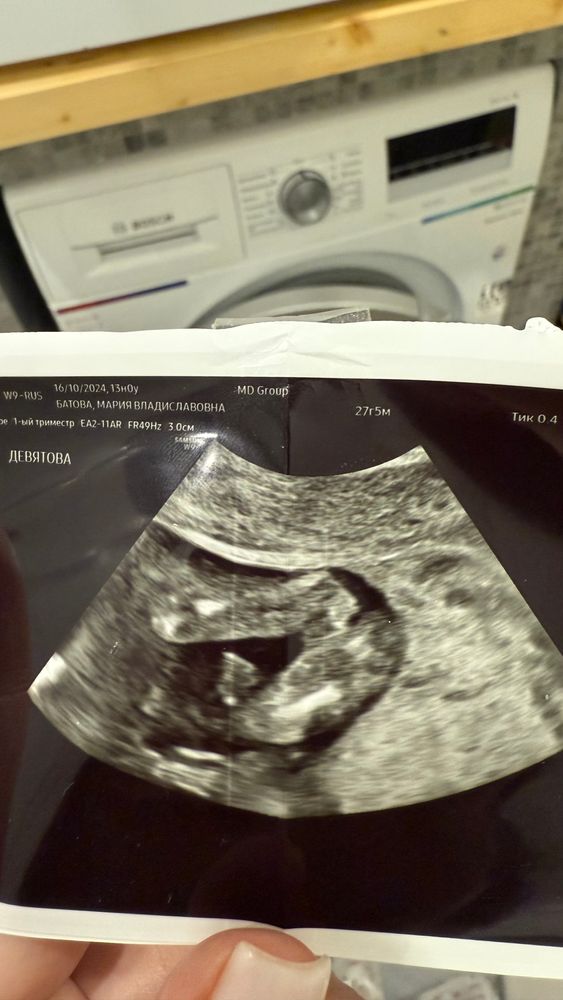

Пол на 12 неделе

На таком сроке это лотерея. Слишком сложно определить, много погрешностией хотите быстро и точно, сдавайте кровь или ждите, пока подрастёт малыш

Мария, на таком сроке очень легко перепутать, слишком маленькое все

Мария, если я не ошибаюсь, до 16 недель у мальчиков и девочек все одинаково :) половой бугорок)

В таком ракурсе нельзя, так бугорок и у тех и у других. К слову мне 2 врача в 12и 13 недель ставили неверный пол ( мальчик). Со средним в 12 недель врач предположил верно ( мальчик)

Катерина, мне предположили девочку, видимо из-за того что ничего не торчит между ножек, но обычно же по наклону полового бугорка смотрят , а не снизу на этом сроке

Мария, да по наклону. Плюсую либо кровь ( но это не 100%), либо ждать 16 недель там уже все видно будет)

Ия, согласна, самый надежный вариант) просто стало интересно, можно ли на таком сроке с этого ракурса сказать что это девочка , из-за того что ничего не торчит

Мария, нет, нельзя

Анастасия, мне предположили девочку из-за того что ничего не торчит между ножек, видимо. А у других я смотрю по наклону бугорка смотрят, а не вид снизу

На таком сроке и у мальчиков, и у девочек все одинаково

По такой фотке пол не скажешь, нужно сбоку смотреть. У них в 12 недель у всех «писюны», только угол отличается) Посмотрите у меня в профиле фотку с узи в 13 недель, как пример

Елизавета, посмотрела) у вас там как раз ракурс сбоку и видно половой бугорок хорошо, а у меня по виду снизу ничего не торчит и врач считает что девочка поэтому

Мария, я бы не была так уверена 🤔 Интересовалась этой темой после первого узи и нигде не нашла информацию, как кроме вида сбоку можно определить пол на сроке до 15 недель